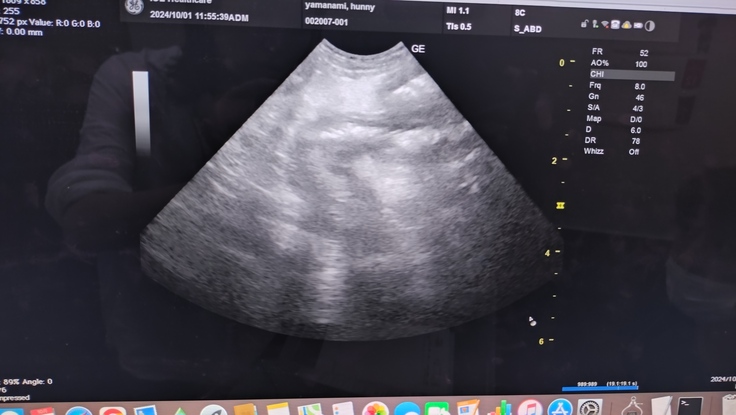

10月1日ママと病院🚗

エコーでまだ腹膜炎の白い影は残るが、腹水は減ったのが確認できた!

CRP1.1までさがりました✨